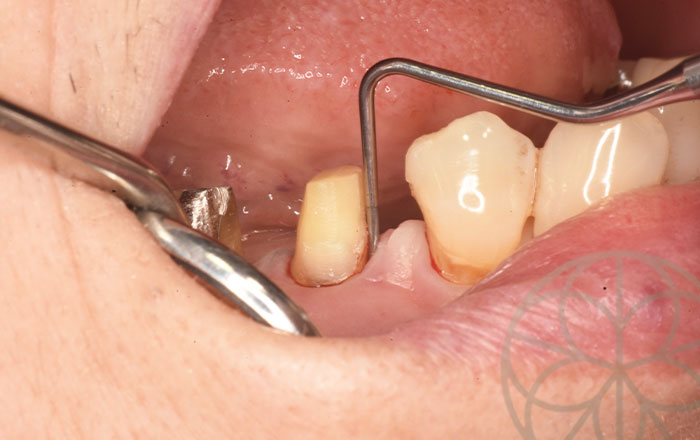

ファーケーションプローブという分岐部病変に使いやすい診査器具で調べるとこの部分のポケットが深く重度に進行していることがわかりました。

歯周組織再生療法時の写真です。

根分岐部は大きく骨欠損していることがわかります。

同部の骨欠損部に人工骨とエムドゲインを塗布して、

歯周組織再生療法を行います。